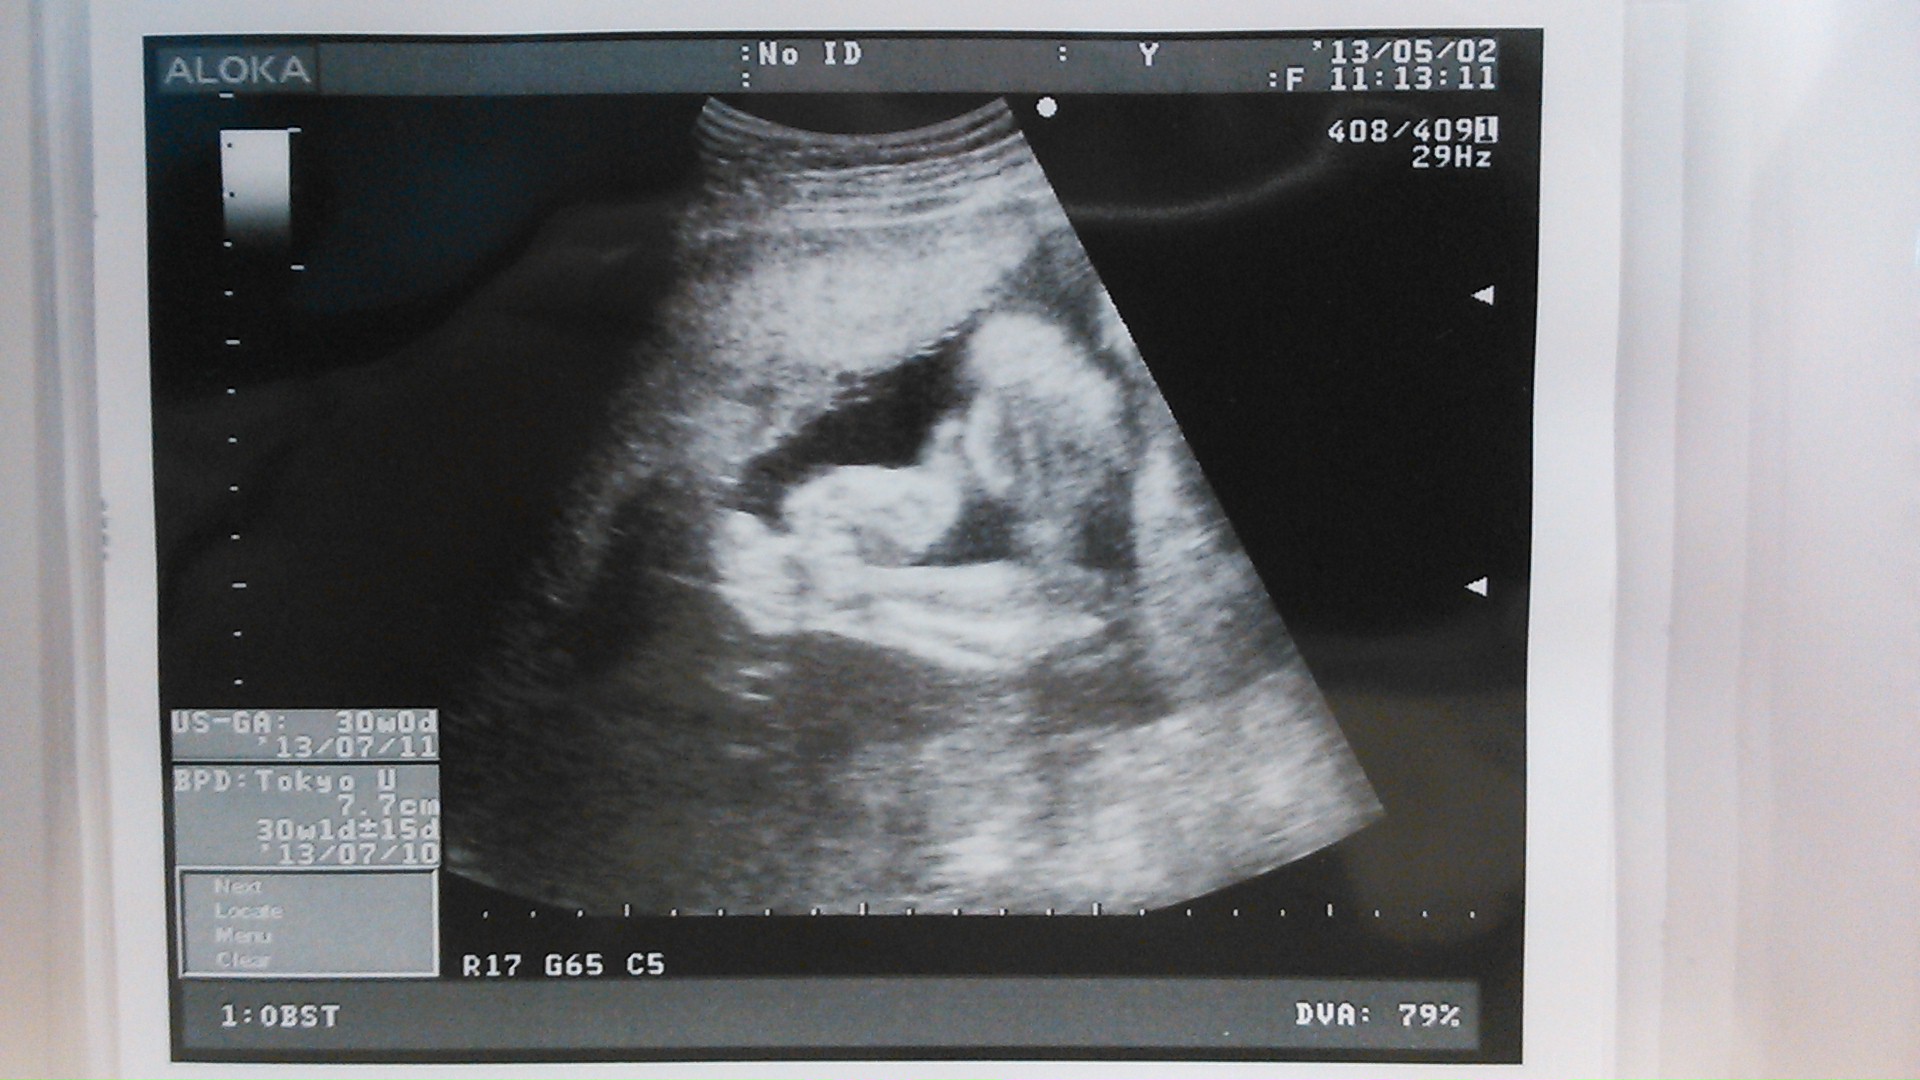

echo